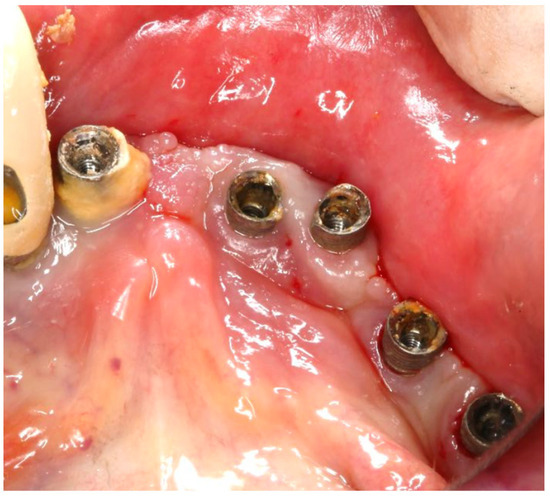

The same protocol mentioned above was used. A five-day antibiotic regimen was administered prior to the surgical procedure. At the surgery, the site had no suppuration and minimal BoP; the implants #33, #36, #37, #44, and #47 were removed, and new implants were placed to provide a new rehabilitation. For the site #41 (without mobility and severe bone loss), following prosthesis and abutment removal (Figure 17a,b), a BSF with two crestal extensions was made around the implants (Figure 17c,d), facilitating optimal access and flap management during the surgical procedure, eliminating the need to retract two flaps, as a midcrestal flap requires. The flap was retracted lingually; the granulation tissue was removed, and the contaminated implant surface fully exposed (Figure 17d).

Figure 17. Step-by-step treatment for peri-implantitis using the iMPACT and Quadrant protocol. (a) Initial clinical evaluation; (b) Removing the abutments for peri-implantitis treatment; (c,d) BSF raised for implant exposition; (e) Insertion of the hinge (pin), which was crewed into the implant; (f) Hinge in position; (g,h) iMPACT adapted to the hinge; (i) iMPACT spinning for implantoplasty; (j) The implant surface was smoothed, and bone around the implant was gently cut (osteotomy); (k) occlusal view showing the osteotomy; (l) implantoplasty finished—implant surface is completely smoothed (machined); (m) Bone graft; (n) Suture and abutments were repositioned.